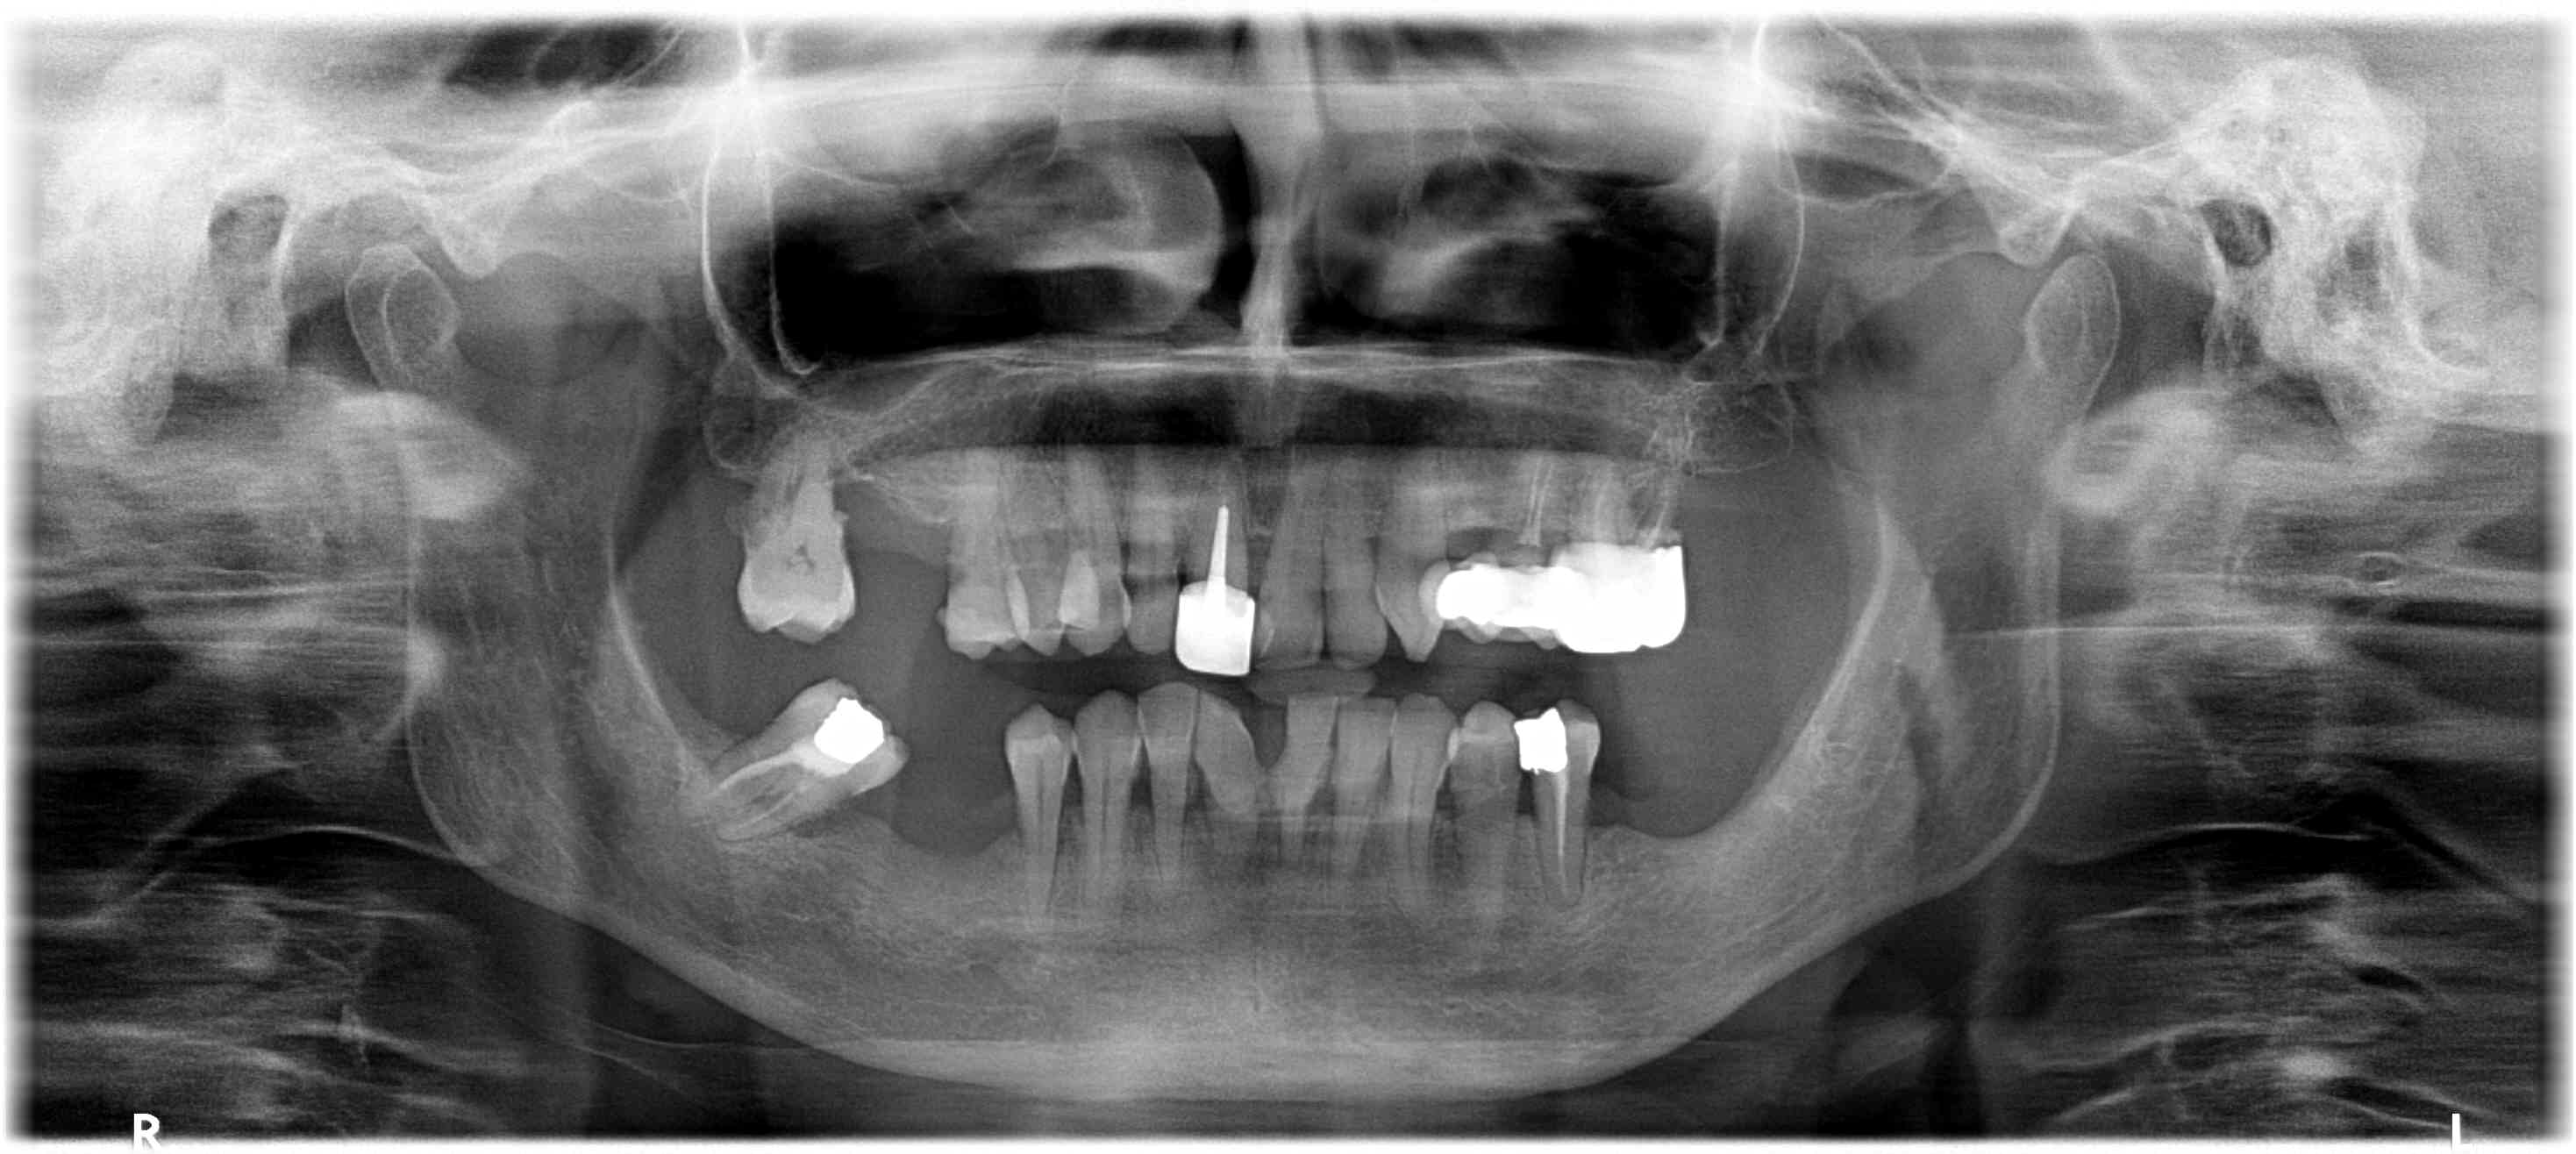

- De réaliser un bilan radiologique : le panoramique dentaire devra être complété par des clichés rétroalvéolaires voire un dentalscanner en cas de doute concernant un foyer infectieux.

Et en pièce jointe, pour aider à la décision pour les "dents douteuses"

En vrai, le curseur est parfois delicat a régler. On se base souvent sur les panoramiques pour les bilans, est ce bien raisonnable ?

non le bilan cône beam devrait être obligatoire

Parodontite chronique scorée à 8/10 :)